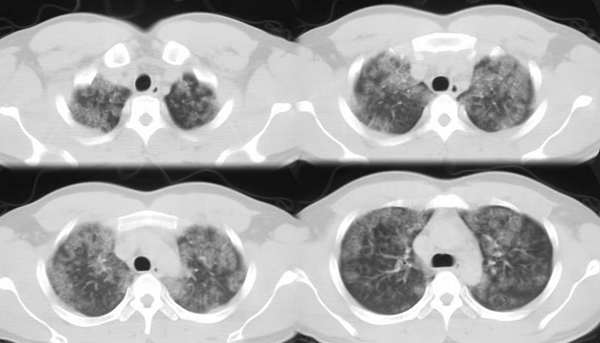

以下是引用ssl1_1在2006-3-2 22:37:00的发言:[br]肺泡蛋白沉积症(外围型)

以下是引用huangaiying1在2006-3-3 16:03:00的发言:[br]双肺弥漫分布的磨玻璃影及小结节影,以双上肺为著,纵隔内未见明显增大的淋巴结影,结合病史,考虑过敏性肺炎

以下是引用guandong在2006-3-4 20:57:00的发言:[br]两肺弥漫分布磨玻璃影,以中外带为主,可见于过敏性肺炎、肺泡蛋白沉着症、农民肺等,但不支持结核。